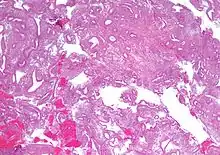

- Atypical endometrial hyperplasia (simple or complex) - Simple or complex architectural changes, with worrisome (atypical) changes in gland cells, including cell stratification, tufting, loss of nuclear polarity, enlarged nuclei, and an increase in mitotic activity. These changes are similar to those seen in true cancer cells, but atypical hyperplasia does not show invasion into the connective tissues, the defining characteristic of cancer. The previously mentioned study found that 22% of patients with atypical hyperplasia eventually developed cancer.[6]